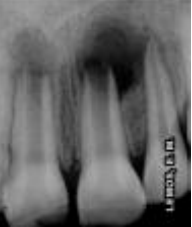

Analisando a imagem radiográfica ao lado, observou-se a presença de lesão periapical nos incisivos superiores. Segundo o relato do caso, a criança sofreu um acidente traumático (queda no toboáguá, batendo a boca no fundo da piscina) há um ano. Clinicamente observou-se uma fratura coronária no dente 11, com envolvendo esmalte, dentina, e no dente 21 fratura de esmalte. Relatou ainda que os dentes ficaram muito moles e que aos poucos a mobilidade cessou. No exame radiográfico observou-se rizogênese incompleta, com presença de lesão em ambos os dentes.

Assinale a alternativa correta quanto ao tratamento corretamente indicados para o paciente e o objetivo do mesmo, respectivamente:

imagem do site www.end o-e.com |